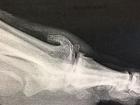

1 - L'ARTHRODESE :

Elle constitue l'intervention de référénce.

Elle supprime immédiatement la douleur (et la mobilité !) mais le réglage de la position est important en maintenant un espace avec le 2° orteil et une rotation neutre.

Le but de l'intervention est de réséquer les ostéophytes, gênant le chaussage et bloquer la première articulation métatarso-phalangienne par avivement des surfaces articulaires et ostéosynthèse par agrafes, vis ou broches.

Des chaussures post-opératoires sont nécessaires 45 jours pour limiter le risque de pseudarthrodèse (défaut de consolidation).